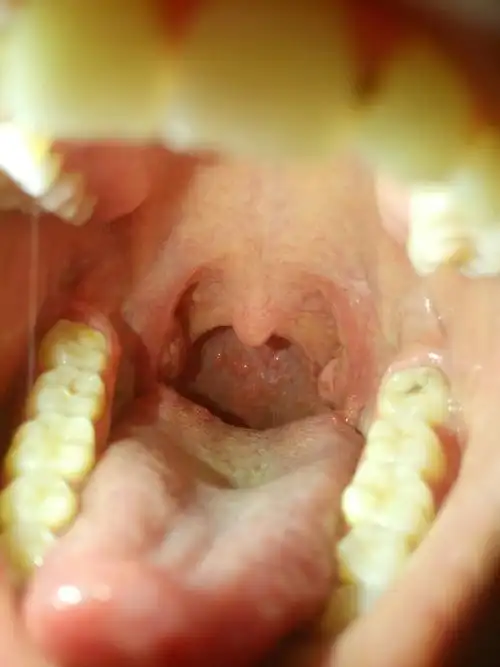

喉咙生痢泡是什么原因引起的

我的嗓子总是起红泡泡,麻烦行家看看这个怎么治.吃药打针都没用.

喉咙里面的这些泡泡怎么回事?

喉咙那里起白泡泡,怎么回事?医生说还要开刀呢.

喉咙严重上火还有泡一个多月了还没有好,现在声音也变了越来越严重了

急慢性咽喉贴咽炎贴喉咙有痰发痒干咳异物感声音嘶哑肿痛滤泡增生》无